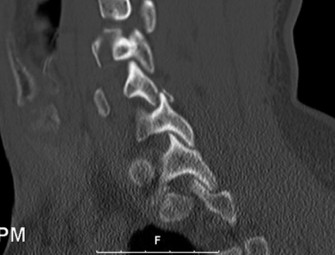

Determine the most appropriate treatment of different types of Hangman’s fractures? CASE 14 A 70-year-old retired, funeral director presents with symptoms of right upper extremity numbness and weakness. He reports that he developed acute neck and right upper arm pain while undergoing a dental procedure. Treatment so far has been nonsteroidal anti-inflammatory medication and physical therapy with cervical traction. While his pain improved with this course of treatment, he has ongoing paresthesias radiating into his right hand and weakness affecting his right upper extremity. Figures 1–20 and 1–21 show a midsagittal and axial image through C6–7, respectively.

The correct answer is (A). Considering the patient’s complaints and the imaging, he most likely has radiculopathy, probably secondary to a disc-osteophyte complex associated with foraminal stenosis at the C6–7 level. There is no suggestion in the history of walking imbalance or dexterity issues in the upper extremities. Thus, a diagnosis of myelopathy is less likely. Furthermore, the degree of spinal compression is mild and not likely (though not impossible) to cause spinal cord dysfunction. An intradural tumor would have a different MRI appearance, likely demonstrating an area of high signal within the parenchymal tissue of the spinal cord itself. A central cord syndrome is an acute spinal cord injury with upper extremities being affected more than lower extremities.

The correct answer is (C). The patient has nerve root compression at the C6–7 level, which would affect the exiting C7 nerve. Weakness of right elbow extension and wrist flexion with sensory loss of the middle finger are the most likely findings.

The correct answer is (D). Both anterior and posterior surgical approaches have been associated with consistently good clinical outcomes in this patient population having single level radiculopathy from foraminal stenosis secondary to a disc-osteophyte complex. Objectives: Did you learn...? Recognize the clinical presentation of cervical radiculopathy associated with a disc-osteophyte complex?